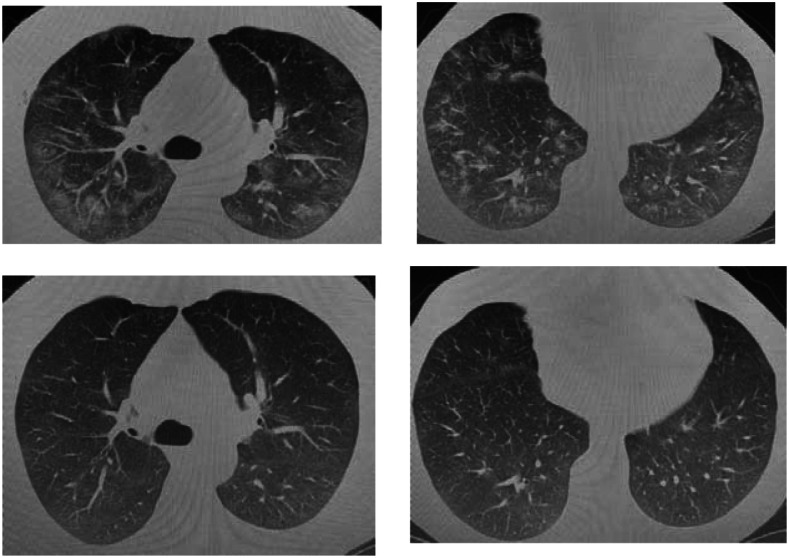

A chest X-ray was acquired after the patient’s respiratory examination. On the same day, chest computed tomography (CT) was performed and small ground-glass nodules were seen, scattered across the two lungs, suggesting viral pneumonia (Figure 1). One day later, a real-time reverse transcription–polymerase chain reaction (RT-PCR) analysis of the patient’s throat swab sample indicated SARS-CoV-2 infection. We hospitalized the patient with a COVID-19 diagnosis. We found that our patient had moderate pneumonia according to the WHO’s classification.9 During hospitalization, Favipiravir (day 1, 2 × 1,600-mg loading dose; afterwards days 2–5, 2 × 600 mg) antiviral treatment was added to the treatment, and dexamethasone and azithromycin (day 1, 1 × 500-mg loading dose; days 2–5, 1 × 250 mg) therapy were used as recommended in the COVID-19 guidelines.10 The patient’s hiccups did not improve for 2 days after treatment initiation and he had insomnia. Chlorpromazine was started for resistant hiccups, which disappeared 12 hours after treatment. Chlorpromazine treatment of hiccups continued for 3 days and there was no complaint after discontinuation of chlorpromazine. After 10 days of treatment, the patient’s symptoms improved significantly and he recovered, as shown with negative RT-PCR. The patient returned for a follow-up 2 months after discharge and reported no recurrent hiccups. Control chest CT scan is shown in Figure 1.

Figure 1.

Computed tomographic chest scans of case 1 (top row) before and (bottom row) after coronavirus disease treatment.